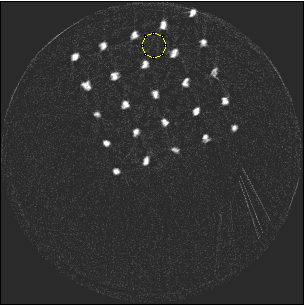

Figure 5 illustrates a single slice spectral reconstruction of the Ti scaffold. Varying levels of streak artefacts can be seen across the spectral reconstructions. The spectral reconstructions for the energy ranges 35 to 80 keV, 55 to 80 keV, and 62 to 80 keV shown in figure 5, exhibit reduced streak artefacts. A region-of-interest (ROI) analysis was performed in the immediate vicinity of the metal region where the streaks are more pronounced. Average attenuation coefficent of air close to zero conveys less regional noise/artefacts. The regional average attenuation coefficient () of the non-metal (air) region in 55 to 80 keV reconstruction (figure 5c) shows reduced artefacts. Even though minor streaks and statistical noise appear in figure 5d due to photon limitation, the artefacts are less pronounced in comparison to the wide energy acquisition in figure 5a.

Using the Ti scaffold sample, a post reconstruction analysis between Si detector (Medipix3.1) operating in Single Pixel Mode (SPM) and CdTe detector (Medipix3RX) operating in CSM was carried out. Figure 6a shows a reconstruction for energy range 30 to 50 keV obtained using Si detector with a detector element size 55 m in SPM. Despite good spatial resolution, artefacts are still prominent. The reconstruction using CdTe detector with a detector element size of 110 m in CSM (figure 6b) shows reduced artefacts comparatively. To obtain the narrow energy range of 35 to 55 keV, the raw counts at 35 to 80 keV and 55 to 80 keV were subtracted.